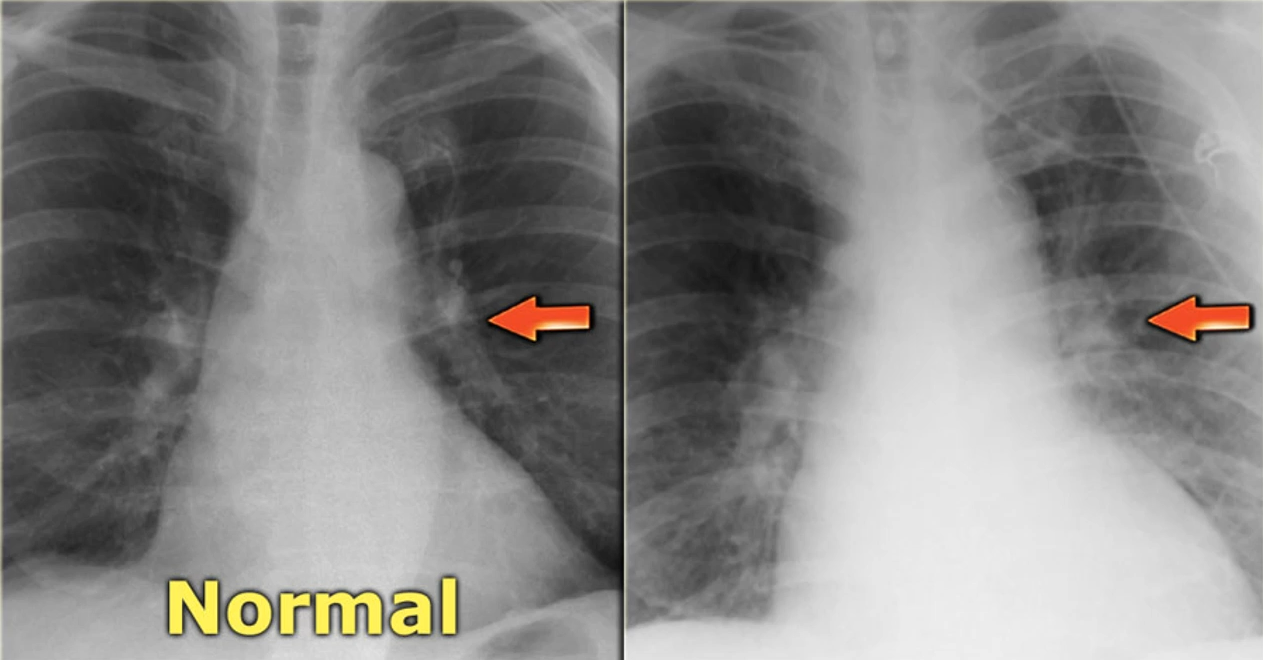

• Chest X-ray:

• patient has to remove all clothes and jewellery from the waist

• the xray machine sends a beam of ionising radiation through an xray tube

• the energy passes through the chest and is absorbed on film to create a picture

• bone and other dense areas show up as light shades of grey

• Chest X-ray - heart failure:

• can look at the size of the myocardium in relation to the mediastinum

• if the heart is enlarged it could indicate heart failure